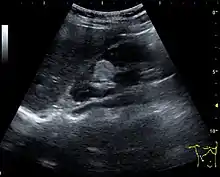

Three methods of scanning can detect Angiomyolipomas: ultrasound, computed tomography (CT), and magnetic resonance imaging (MRI).[5] Ultrasound is standard and is particularly sensitive to the fat in Angiomyolipomas, but less so to the solid components. However, accurate measurements are hard to make with ultrasound, particularly if the Angiomyolipoma is near the surface of the kidney (grade III).[4] CT is very detailed and fast, and allows accurate measurement. However, it exposes the patient to radiation and the dangers that a contrast dye used to aid the scanning may itself harm the kidneys. MRI is safer than CT, but many patients (particularly those with the learning difficulties or behavioural problems found in tuberous sclerosis) require sedation or general anaesthesia, and the scan cannot be performed quickly.[3] Some other kidney tumours contain fat, so the presence of fat is not diagnostic. Distinguishing a fat-poor angiomyolipoma from a renal cell carcinoma (RCC) can be difficult.[6] Both minimal fat AMLs and 80% of the clear-cell type of RCCs display signal drop on an out-of-phase MRI sequence compared to in-phase.[7] Thus, a lesion growing at greater than 5 mm per year may warrant a biopsy for diagnosis.[3]